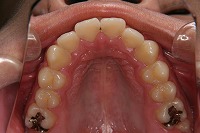

上顎

反対咬合と下顎が出ている事を主訴に来院された、初診時18歳1か月の男性です。診断「上顎骨の後方位による骨格性反対咬合」非抜歯での矯正治療と、下顎を後退させる外科手術を併用して治療を行いました。